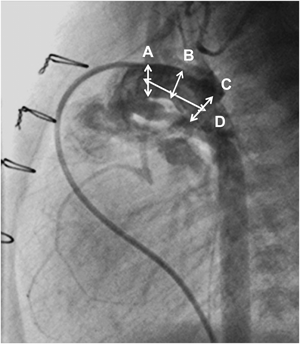

The main pulmonary arteriogram revealed the constriction of the pulmonary arterial side of the arterial duct (AD), which was not covered by the previously implanted stent (A; arrow). The guide wire was formed in vitro into an inverted U-shape to fit the curvature of the AD (B, arrows). During the procedure, blood pressure was maintained at a higher level after intravenous infusion of epinephrine (10 µg), and a stent (6 mm in diameter and 18 mm in length) (Palmaz Genesis® 1860) was delivered into the AD by bare delivery (C) and implanted (D).

2006年10月から2013年10月の間に当院で12症例(Table 5)に施行したDSの最中または後に生じた合併症・問題点をTable 6に示す.最多の問題は手技中の血圧低下であり,12症例中7症例に認められ,その内の5症例はHLHSであった.特に大動脈弁閉鎖では血圧低下から冠血流が低下して重篤な心機能低下をきたし得るので,Bare stent deliveryやエピネフリン静注などの対応を施して手技に臨む必要がある.